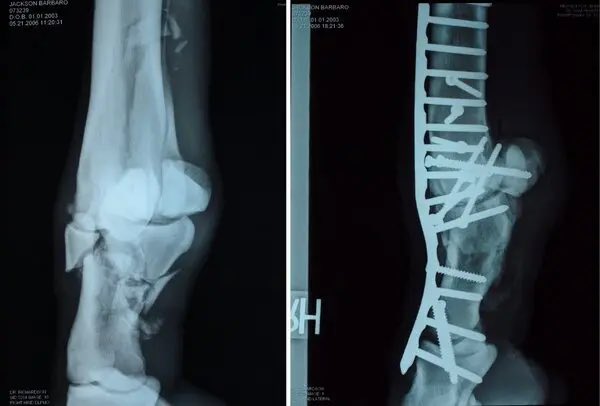

الأجابة تبدأ من تكوين الخيل التشريحي لأن الحصان ليس لديه عضلات في ساقيه تحت الركبتين والعرقوب.

بل يتكون الجزء السفلي من الساق من العظام والأوتار والأربطة والغضاريف والجلد والشعر كما في الصورة أمامك بالضبط

كما أن عظامه خفيفة نسبياً وتحتوي أرجله على حوالي 80 من أصل 205 عظمة في جسمه بالكامل.

وبالتالي إذا انكسر الجزء السفلي من ساق الحصان ،فإن العظام الموجودة فيه لا تنكسر فقط؛ بل غالبا ما تتهشم تماما.

هذا يجعل من المستحيل إصلاحها أو إعادتها إلى شكلها الأصلي في بعض الحالات حتى لو تم تجميعهم بطريقة ما ، فإن الحصان سينتهي حتماً بعظم ثابت بشكل سيء.